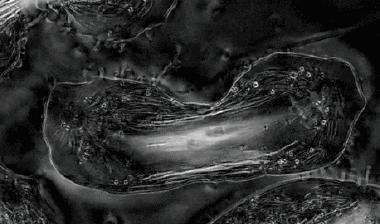

海拉细胞增殖分裂